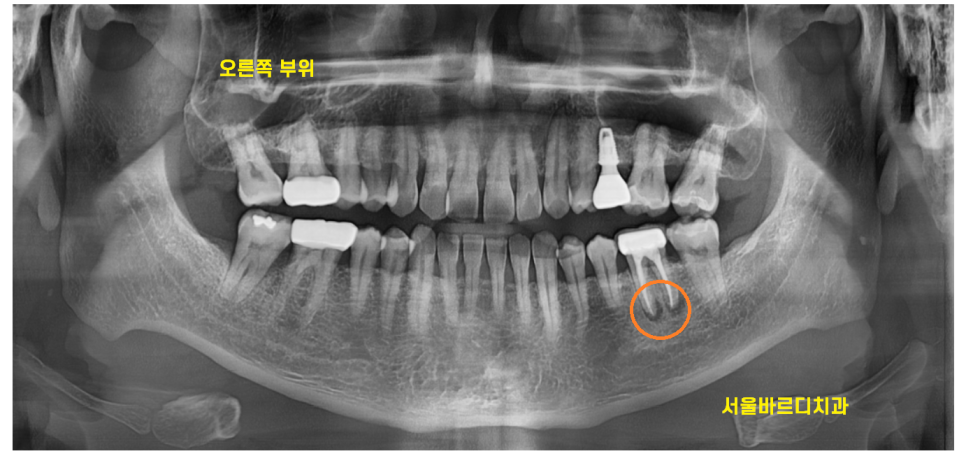

엑스레이를 찍어보았는데

오른쪽 위에 부분에 크게 충치라던가

잇몸 염증은 보이지 않았는데요.

저는 오히려 왼쪽 아래가

더 눈에 잘 들어오더라고요.